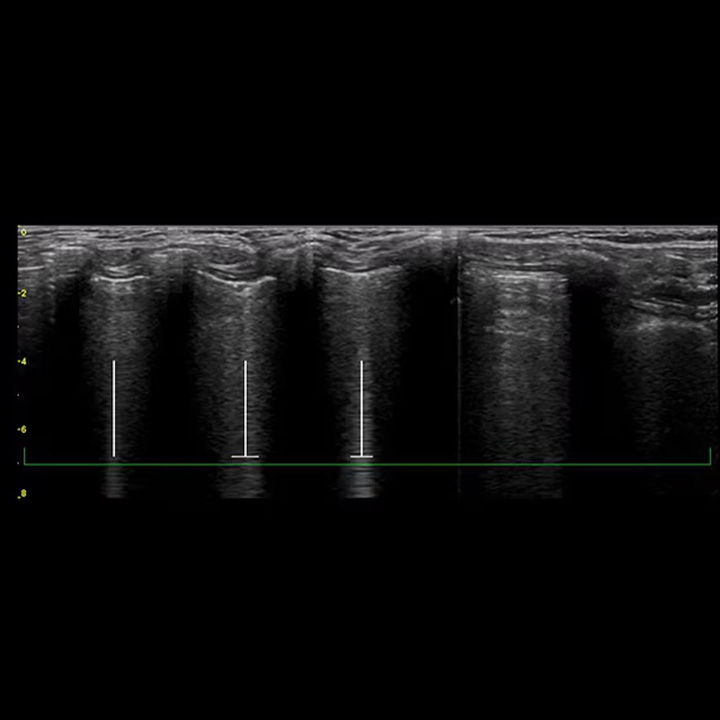

Highlight and count B-lines, in real time

With the Auto B-Lines* tool, you can calculate overall lung score in one step. Use it in conjunction with Lung Sweep to highlight B-lines and display the frame with the most B-lines per rib space.